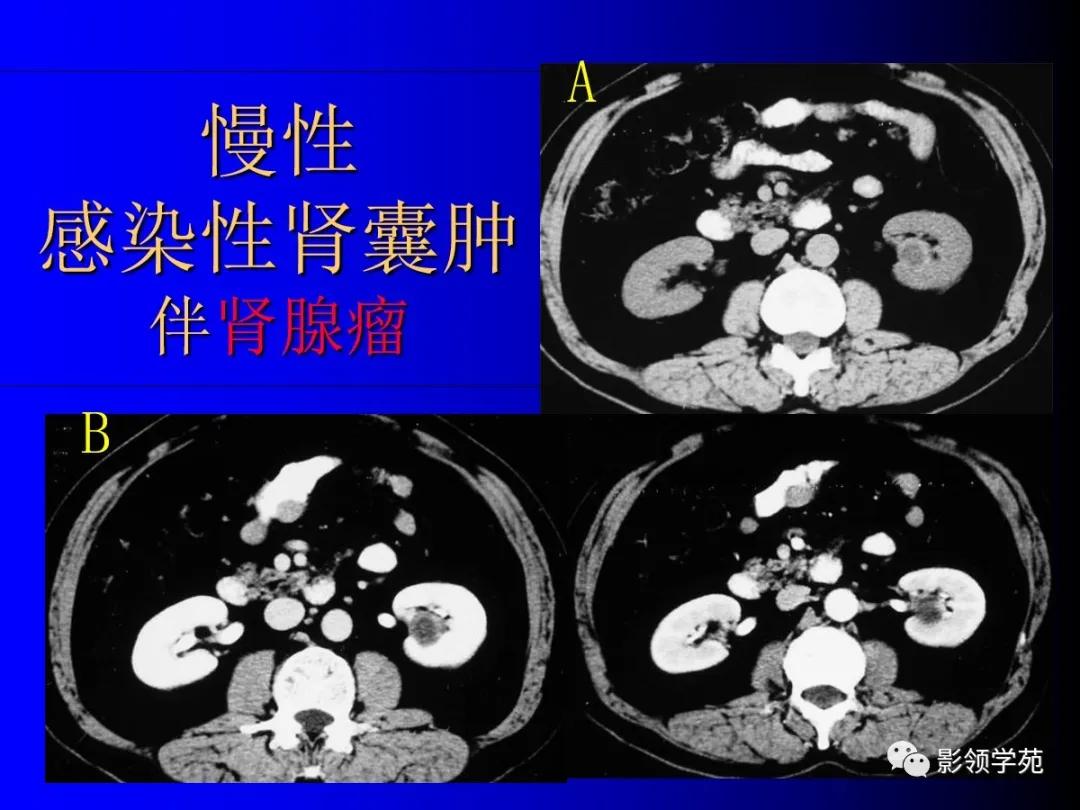

2、复杂性肾囊肿(Complicated cysts)

肾囊肿内含有血液、脓液、间隔或钙化

感染性囊肿。

12、肾癌囊变和多房囊性肾癌

肾癌部分囊变易鉴别,少数需和感染性囊肿鉴别。